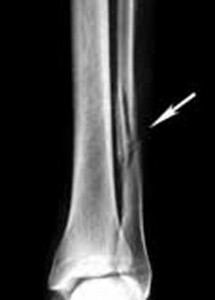

Συμπτώματα κατάγματος της περόνης

Συμπτώματα στην περόνη περιλαμβάνουν τοπική υπερευαισθησία και πόνο που εντείνεται προς τα κάτω κατά την βάδιση αλλά δεν είναι όσο επίπονα όσο τα συμπτώματα κατάγματος της κνήμης.